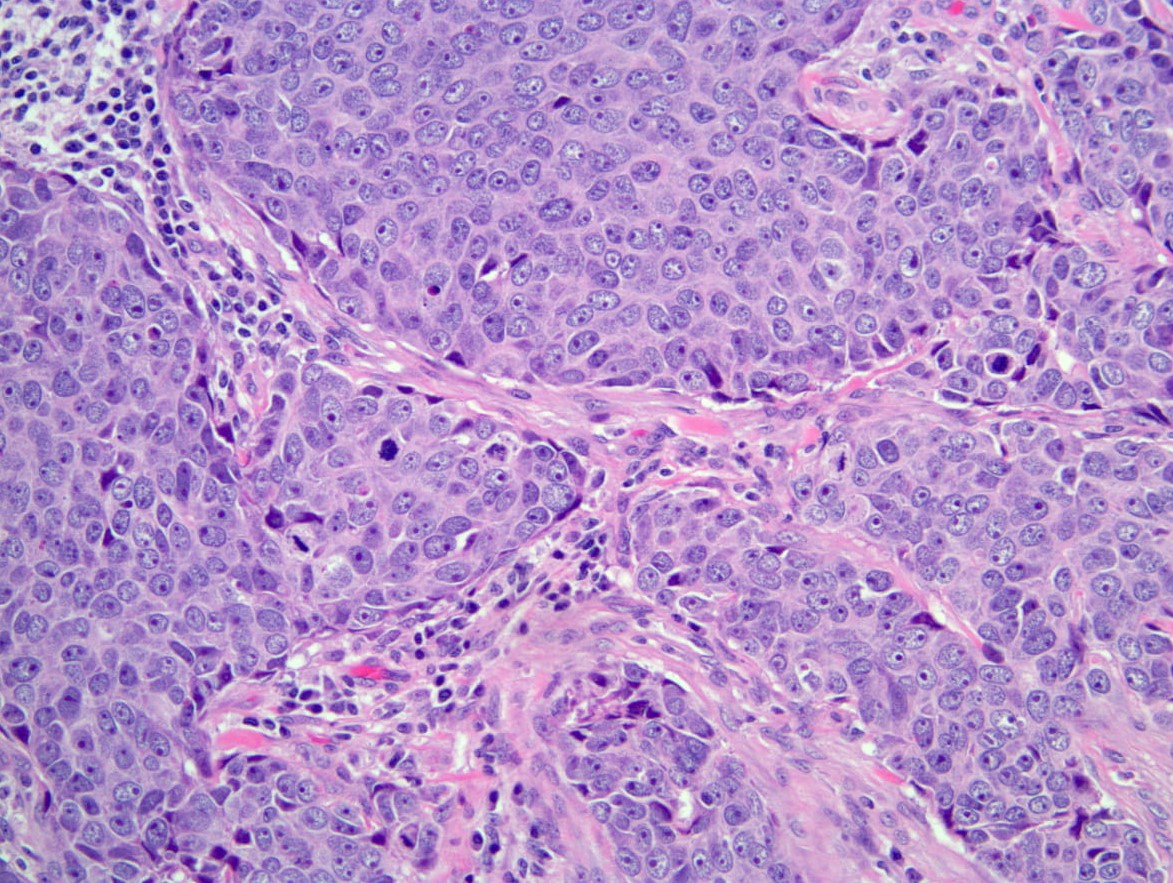

Imaging and Staging for Stomach Malignancy

- Endoscopic ultrasonography (EUS) is a currently the mainstay in diagnosis and staging of gastric tumors.

- EUS FNA offers precise diagnosis for primary tumors, local invasion, and lymph node sampling.